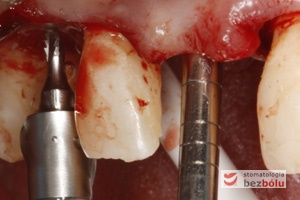

Proces implantacji - pierwsze wiertło pilotowe Lindemana pozwala ocenić gęstość kości i wyznaczyć pozycję implantu

Proces implantacji – pierwsze wiertło pilotowe Lindemana pozwala ocenić gęstość kości i wyznaczyć pozycję implantu

Ustalenie pozycji implantu - wiertło Lindemana wyznacza nachylenie i oś długą dla wprowadzanego implantu

Ustalenie pozycji implantu – wiertło Lindemana wyznacza nachylenie i oś długą dla wprowadzanego implantu